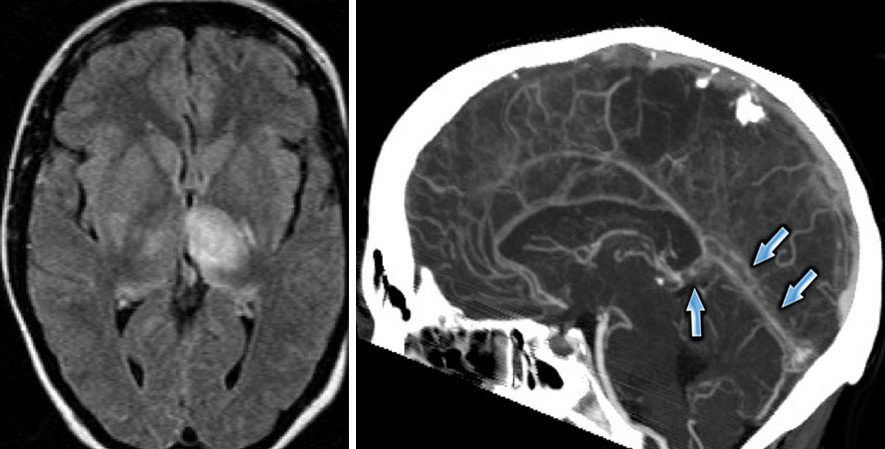

Наиболее доступным и информативным методом для подтверждения диагноза является МРТ. Если это возможно, пациенту назначают КТ, что позволяет не только установить наличие тромба в синусе, но и выявить сопутствующие изменения в мозговой ткани, такие как отек, некроз или кровоизлияние.